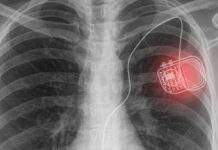

Tech: A novel active photonic wireless system to power medical implants

IMAGE: The use of medical implants in human bodies generates the need for...